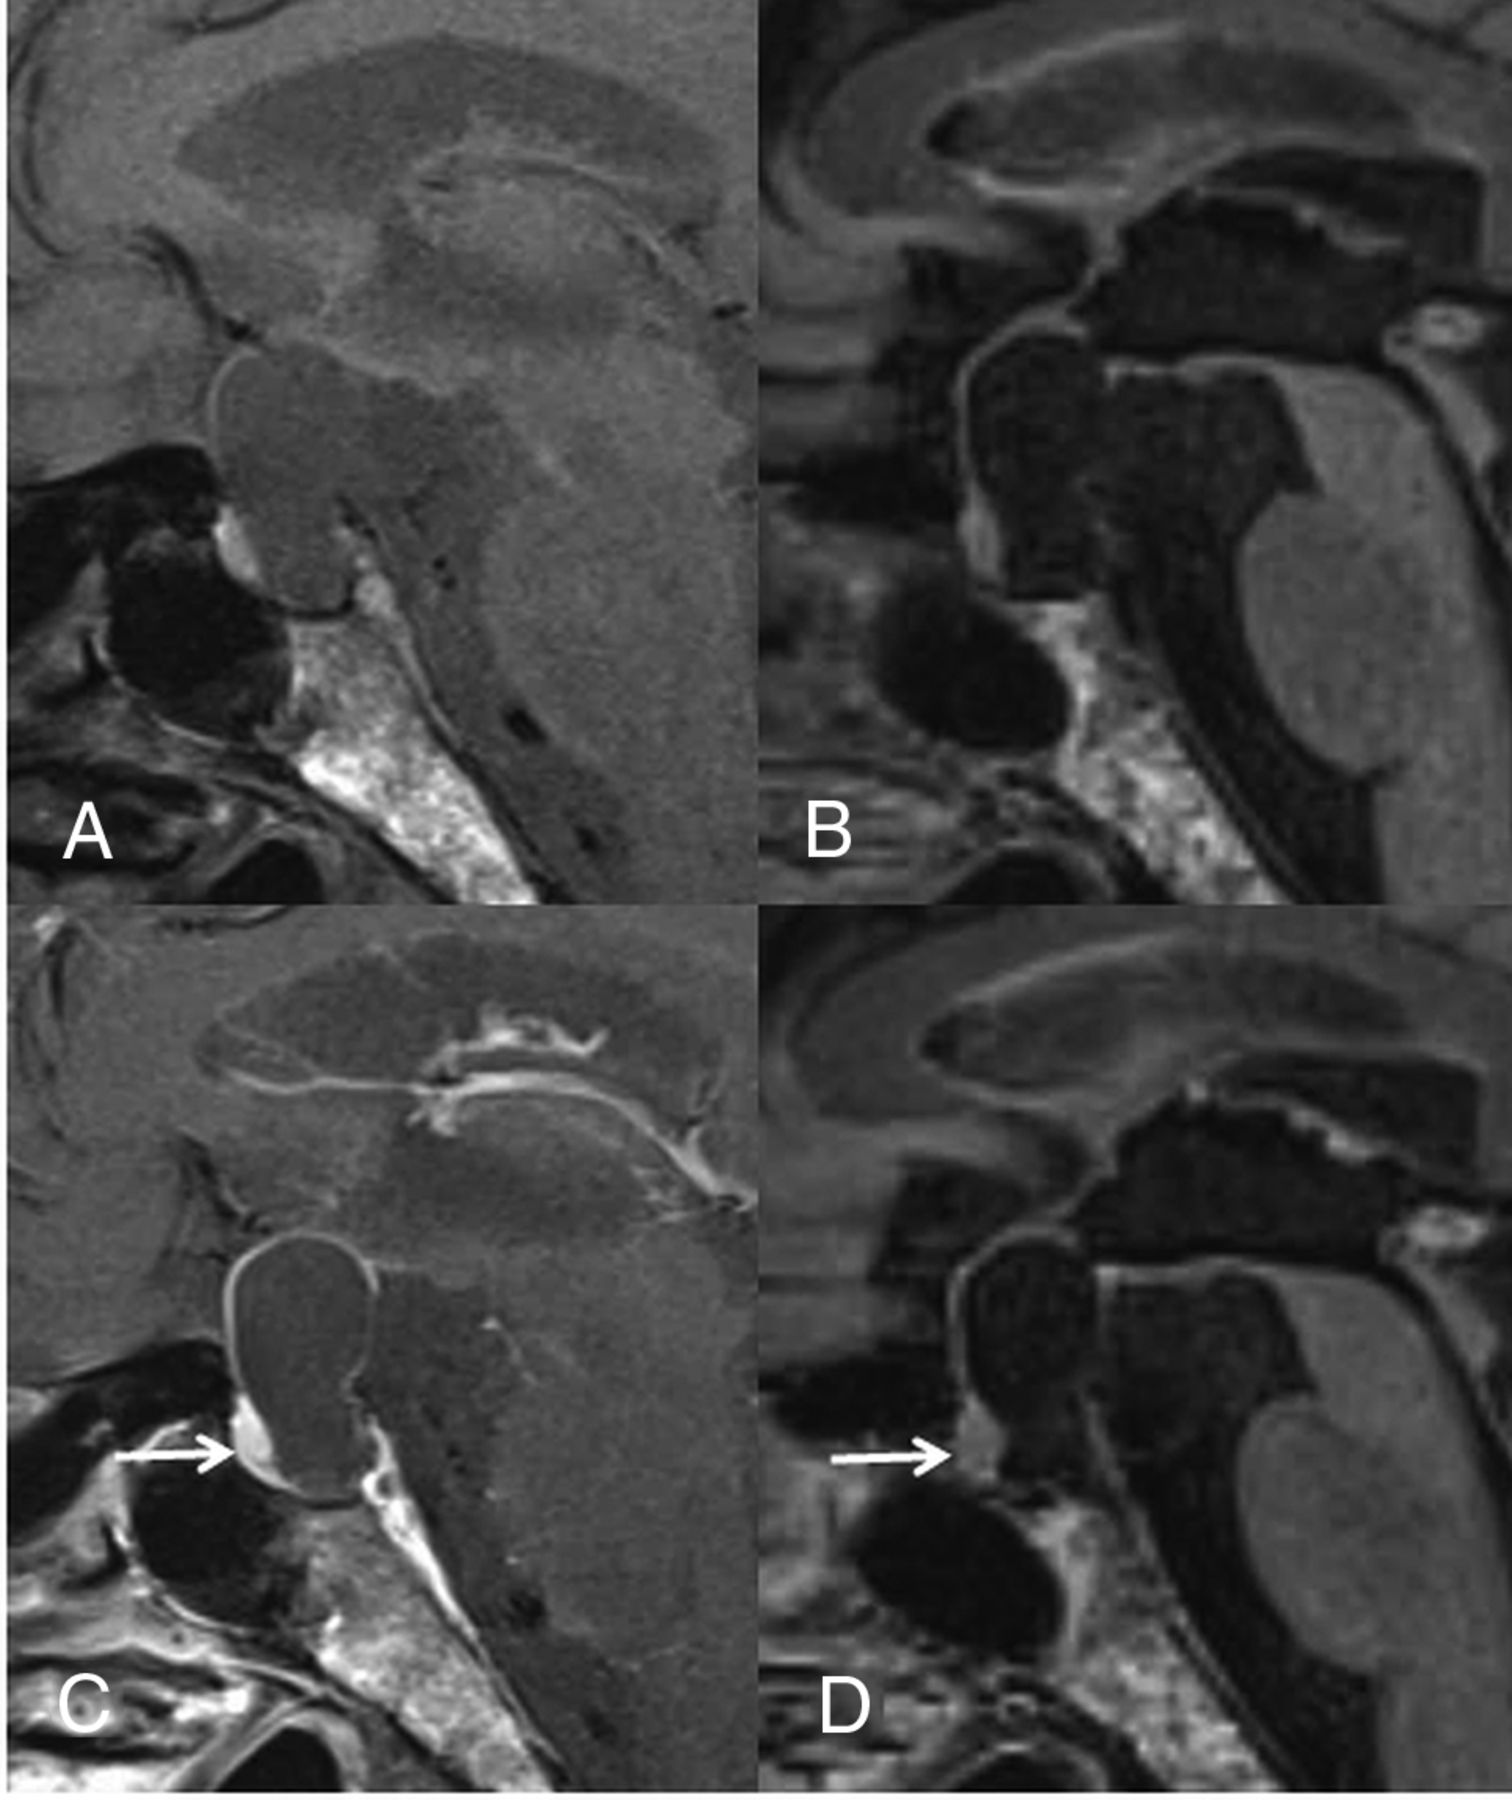

A 23-year-old woman with RCC. Compared with the precontrast T1WI (A), the postcontrast T1WI (C) demonstrates enhancement in most of the cyst wall (grade 2). Compared with the precontrast 3D T2-FLAIR image (B), the postcontrast 3D T2-FLAIR image (D) shows grade 1 enhancement of some of the cyst wall (arrow). In the blinded reading study, the confidence scale of this lesion was probably an RCC (scale 2) at both the first and second interpretation sessions.

A 40-year-old woman with an RCC. On the postcontrast T1WI (C) compared with the precontrast T1WI (A), the cyst wall is enhanced (grade 2), as is the pituitary gland. Unlike the precontrast 3D T2-FLAIR image (B), the postcontrast image (D) shows no contrast enhancement (grade 0). Different from the postcontrast T1WI (C), the pituitary gland is not enhanced on the postcontrast 3D T2-FLAIR image (arrow in D). The observer judged this lesion as equivocal (scale 3) at the conventional MR interpretation, whereas the confidence level was changed to probably an RCC (scale 2) by the addition of 3D T2-FLAIR interpretation.

A 60-year-old man with RCC. On the postcontrast T1WI (C) compared with the precontrast T1WI (A), the cyst wall is enhanced (grade 2) and a solid enhanced area is seen (arrow). Unlike the precontrast 3D T2-FLAIR image (B), the postcontrast image (D) shows no contrast enhancement of the wall (grade 0) and the solid area (arrow). The observer judged this lesion as probably a CCP (scale 4) at the conventional MR interpretation, whereas the confidence level was changed to probably an RCC (scale 2) by the addition of 3D T2-FLAIR interpretation.